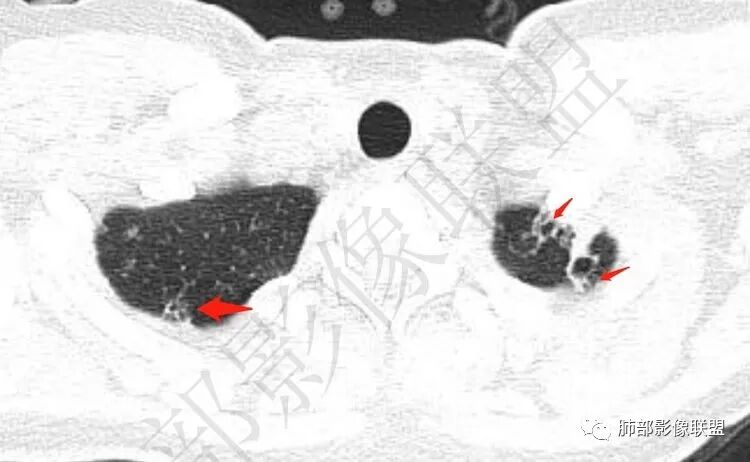

双肺上叶多发结节影及纤维索条影,部分结节内部可见空洞形成,形态欠规则,洞壁厚薄均匀,以胸膜下分布为主,多灶性,多态性,临床年轻女性,体检发现,考虑结核,寄生虫?NTM.

双肺上叶尖段分布为主多发囊腔伴斑点,斑片影,囊腔壁不规则,部分内见分隔。考虑结核可能

两肺多发囊或空洞(部分腔内不干净可见间隔影)+多发结节 (右侧胸膜下的结节显著)+左肺尖斑片影。年轻女性,体检发现。考虑结核?鉴别PLCH(奇异囊加结节,吸烟男性多见),转移瘤(要有原发肿瘤病史)

双肺上叶多发结节影,形态不规则,部分结节内部可见空洞形成,洞壁薄,胸膜下分布为主,年轻女性,体检发现,考虑结核

双肺上叶多发结节影,形态不规则,部分结节内部可见空洞形成,洞壁薄,胸膜下分布为主,年轻女性,体检发现,考虑朗格汉斯组织细胞增生症。鉴别NTM.LAM

2.双肺多发薄壁空洞影、条索影及结节影,边界较清楚,密度偏高不柔和,散乱,但有成簇倾向或堆积感,胸膜下分布为主,双肺上叶分布为主。

3.空洞相当不规则,缺乏张力,未见血管穿行,未见壁结节,未见液平。

4.双肺门及纵隔未见肿大淋巴结。未见胸腔积液。